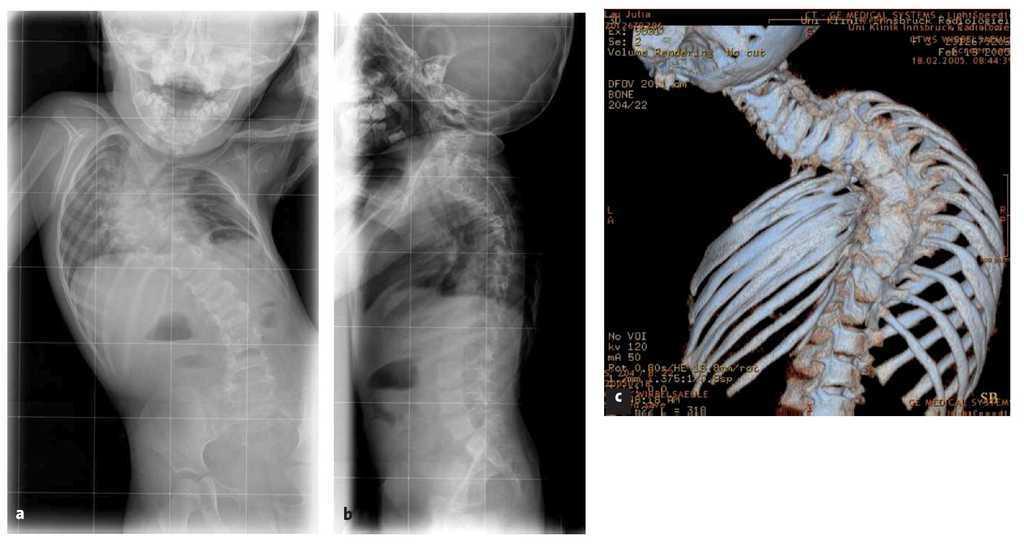

La indicación para la intervención fue en 16 casos una escoliosis congénita (figs. 24a-24c), en once casos una escoliosis neurológica y en doce casos una EIP. Las curvas se determinaron según Cobb. El ángulo de Cobb antes de la intervención medía un promedio de 65º (45-130º), y después de la intervención, un promedio de 32º (25-75º). En 18 pacientes tratamos una escoliosis torácica, en 18 pacientes una toracolumbar y en tres pacientes una lumbar (mielomeningocele). En 18 casos se utilizó un implante «costilla a costilla», en cinco casos un sistema de barra doble hasta la pelvis y en 18 casos un sistema híbrido (figs. 25 y 26).

Figuras 24a a 24c. a) Radiografía anteroposterior preoperatoria de una escoliosis congénita grave con sinostosis costales, hemivértebras, barra vertebral no segmentada y vértebra en mariposa. b) Radiografía lateral preoperatoria. c) TC tridimensional con reconstrucción. En los casos de deformidades graves puede resultar útil para la planificación de la intervención un modelo confeccionado a partir de estos datos.